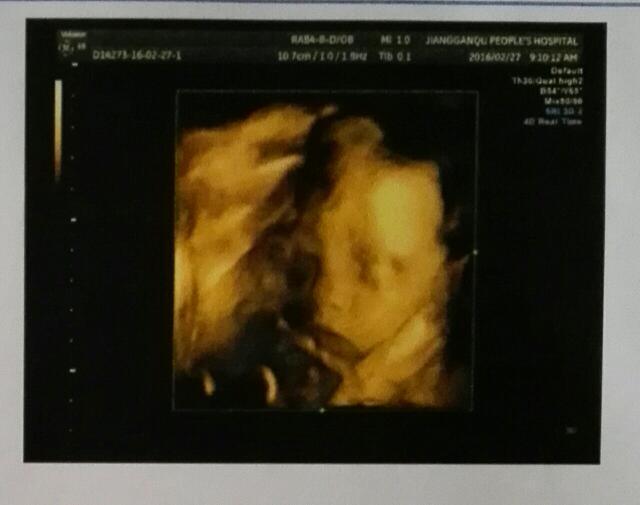

孕40周+0天 LV.4恭喜宝妈,愿宝宝健康成长足月出生,接三维顺利通过^_^

宝宝9岁11天 LV.2恭喜恭喜[哈哈],其实因为我是看到你三维单上面的qual high2人家说那是表示男宝的意思

宝宝9岁7个月23天 LV.6什么意思?qual high2